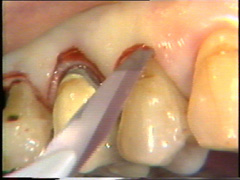

En bucal del canino la bolsa es poco profunda y aquí la incisión se ubica más cerca en de la gingiva del diente. En el lateral la insición se ubica más hacia apical de la superficie del diente.

La intención de este corte es separar los tejidos adyascentes del diente (sanos) del  tejido periodontal infectado (tejido de granulación, cemento infectado y cálculo)